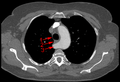

Aberrant subclavian artery at axial CT-scan. (1) trachea, (2) esophagus, (3) Aberrant subclavian artery.